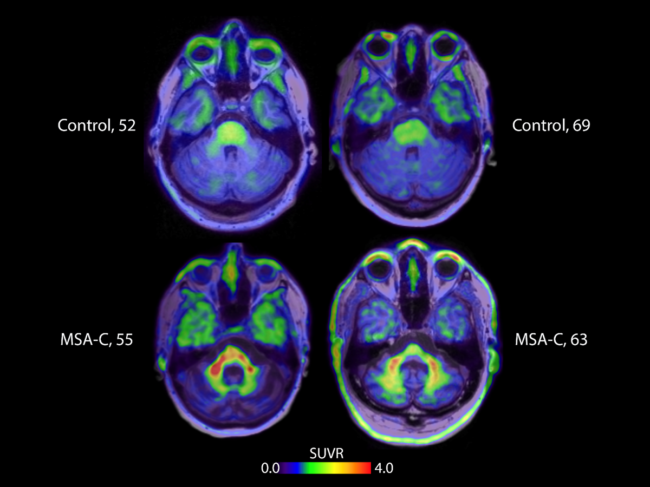

PET images of brains showing alpha-synuclein

AC Immune reports images of alpha-synuclein in human brain using new PET tracer

At the AD/PD 2022 international conference on Alzheimer’s and Parkinson’s Diseases, AC Immune SA presented images showing its positron emission tomography (PET) tracer detecting pathological alpha-synuclein (a-syn) in human subjects’ brains. The abnormal accumulation of a-syn, a natively unfolded and soluble presynaptic protein, is a neuropathological feature of neurodegenerative disorders. Read More